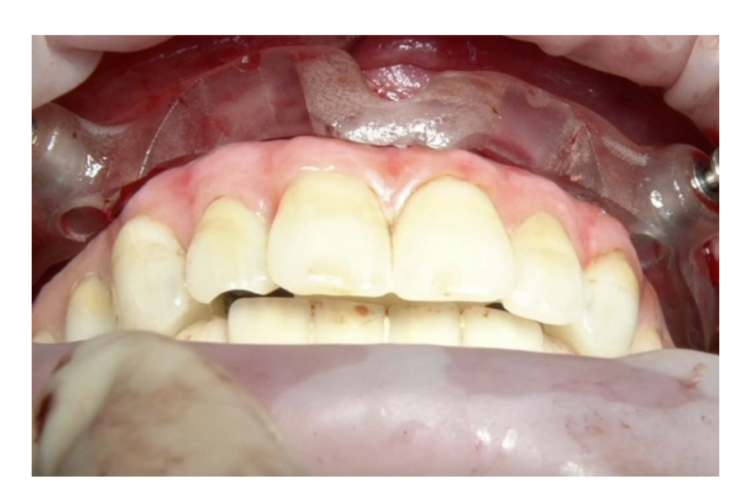

Многоабатментные единицы были прикреплены к имплантатам, и лоскут был зашит. Была доставлена фиксированная, удерживаемая винтами временная реставрация без консоли. Временная реставрация, основанная на установке верхней челюсти, была обработана из PMMA (поли(mетилметакрилат)) и доработана перед доставкой. Временная реставрация была переработана в ротовой полости пациента, используя базовую часть многоразового хирургического шаблона в качестве ориентира для вертикального размера окклюзии и центрового соотношения. Пациент проверялся каждые 2 недели (Рисунки 12–14).

Диагностическая терапия была направлена на переобучение пациента, который был беззубым в течение нескольких лет. Были запланированы немедленные, диагностические, полные съемные верхние и нижние протезы. Этот первый этап был полностью аналогичным. Предварительные слепки были сняты с помощью альгината для отливки учебных моделей. Окончательные слепки были сняты с помощью индивидуального ложки для слепков. Центрическая связь и вертикальное измерение окклюзии были зафиксированы с использованием маневра Досона и фонетических звуков соответственно. Мастермодели были установлены в полу-регулируемом артикуляторе с помощью лицевой дуги. После этого немедленный съемный протез был завершен с использованием задних зубов с углом наклона бугорков 0 градусов, чтобы позволить перемещение нижней челюсти. В день первой операции пациенту была проведена местная анестезия (4% артикаин с адреналином 1/100,000, Septanest, Septodont, Матаро, Испания). Все оставшиеся зубы были аккуратно удалены, и костный гребень был моделирован. Немедленный, диагностический, полный съемный протез был затем передан. Основание и окклюзия были отрегулированы, и пациент наблюдался каждые две недели в течение четырех месяцев. На каждом осмотре окклюзия регулировалась для нахождения правильного положения нижней челюсти, без изменения вертикального измерения окклюзии. Через четыре месяца пациент был доволен новой функцией и эстетикой. Следующим шагом было планирование установки имплантатов, ориентированных на протезирование. Существующие, диагностические, функционализированные съемные протезы были дублированы и использованы в качестве индивидуальных ложек для слепков для снятия новых окончательных слепков. Для установки мастермоделей и дубликатов в артикуляторе использовалась техника перекрестного монтажа, сохраняя центровую связь и актуальное вертикальное измерение окклюзии. Наконец, новые временные протезы были изготовлены с полностью анатомической окклюзией (Рисунок 3). На этом этапе была обеспечена двусторонняя сбалансированная окклюзия у всех леченых пациентов.